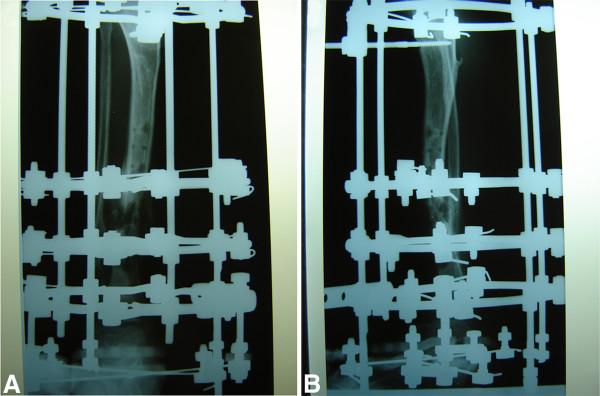

We report a nine-year-old Caucasian girl who had hereditary motor and sensory neuropathy type I and who was admitted with a grade I open tibia fracture after a fall from a small height. Plain radiographs showed a dislocated tibia and fibula fracture. An open reduction with internal fixation with a compression plate osteosynthesis was performed, and soft tissue debridement combined with an external fixateur was undertaken. Three months later, she was re-admitted with localized swelling and signs of a local soft tissue infection in the middle of her tibia. Plain radiographs showed a non-union of the tibia fracture, and microbiological analysis confirmed a wound infection with cefuroxime-sensitive Staphylococcus aureus. Because of the non-union, the osteosynthesis was replaced with an Ilizarov external fixateur, and appropriate antibiotic therapy was initiated. Four months after the initial accident, the fracture was consolidated and we removed the external fixateur.

我们报告一名9岁的白种女孩,她患有I型遗传性运动和感觉神经病变,因从低处跌落导致I级开放性胫骨骨折入院。X线平片显示胫骨和腓骨骨折脱位。进行了切开复位并用加压钢板内固定,同时进行了软组织清创并结合外固定架。三个月后,她再次入院,胫骨中部出现局部肿胀和局部软组织感染迹象。X线平片显示胫骨骨折不愈合,微生物分析证实伤口感染了对头孢呋辛敏感的金黄色葡萄球菌。由于骨折不愈合,将内固定换成了伊里扎洛夫外固定架,并开始了适当的抗生素治疗。初次事故四个月后,骨折愈合,我们拆除了外固定架。